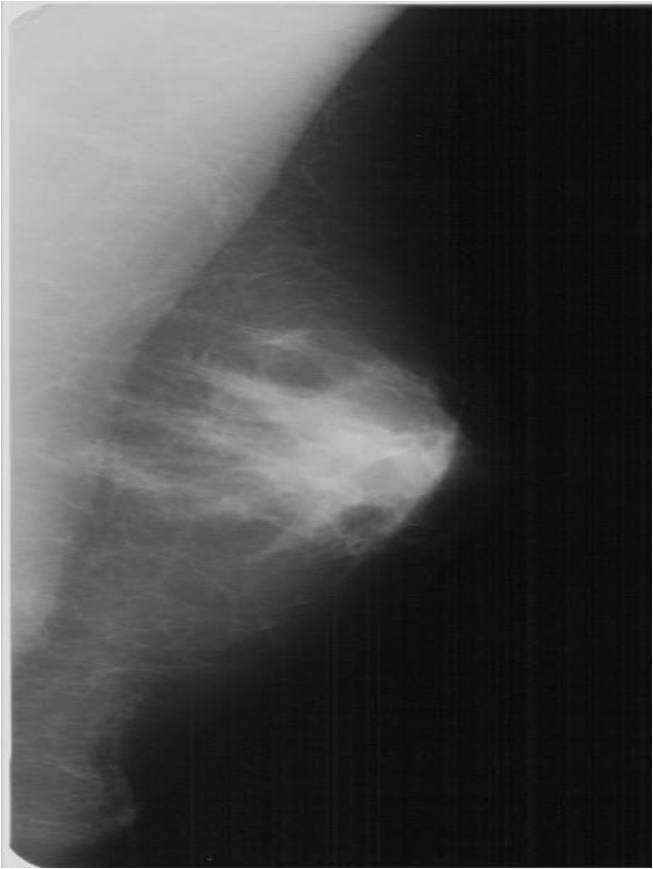

The soft-tissue lesions can appear as well-defined, rounded or oval shaped (Pictures 13.,14.) or as ill-defined, star-shaped masses (Picture 15.). Rounded or oval lesions are in most cases benign and their malignant proliferation is rare, they do not require surgical removal. These lesions are usually cysts and fibroadenomas, at other times hamartomas, lipomas and at very few times malignant tumors.

Star-shaped lesions are very typical of malignant tumors.

o “White star”: describes the tumor body with dense spiculations of various lengths appearing around the core = carcinoma

o “Black star”: there is no tumor body, the central part is transparent. The spiculations are arched, long and thin. These usually do not indicate the entity of the lesion; they can either be benign or malignant. Examples are lobular carcinoma, post-radiation scar tissue, fatty necrosis or postoperative scar tissue (patient history is indicative!).